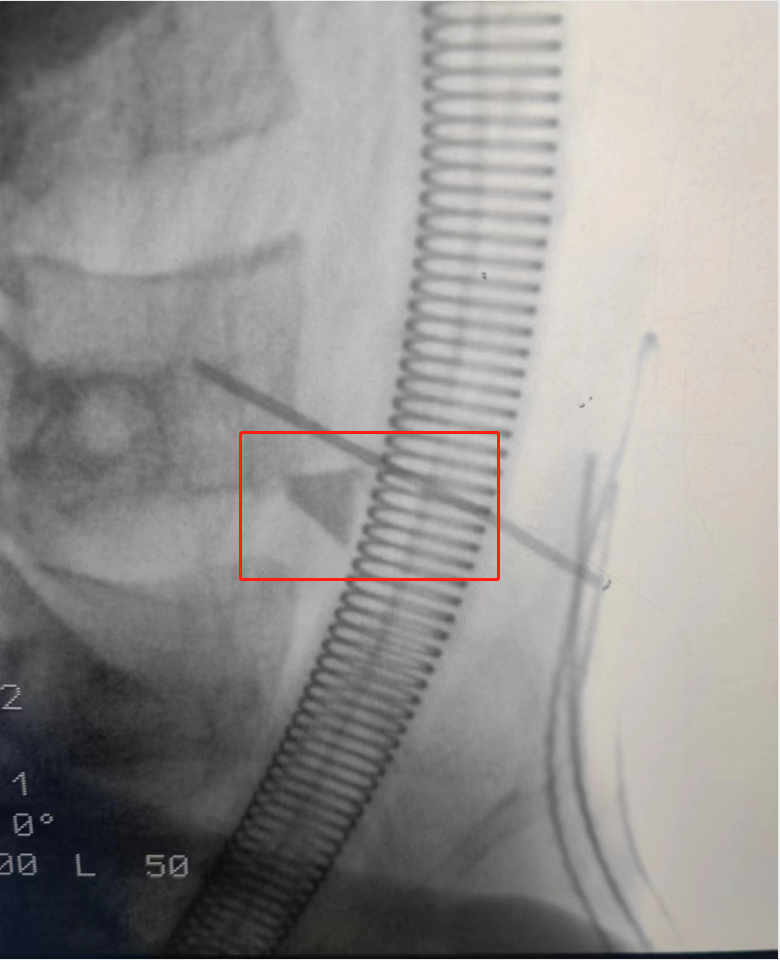

手术当天,耳鼻咽喉头颈外科团队成员密切配合,术中该异物靠近侧颈动脉,后借助C臂影像设备先行大血管解剖保护,探查创面,见组织裂伤及淤血明显,于颈椎前筋膜及颈椎前肌群离断处及周围反复探查,未找到异物。经测量异物近端距离颈部体表较深,可谓深藏不露。在C臂影像引导下探查到,颈椎前前筋膜离断处上方发现梯形诱明玻璃碎片,大小约1.1cm×0.8c×0.1cm,经过团队的努力,最终安全取出异物。